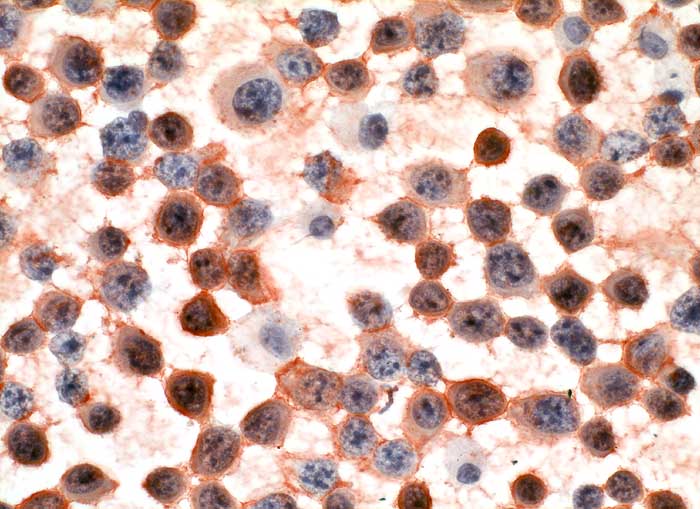

PathoPic – image database / PathoPic ID 6108 - wenig differenziertes multiples Myelom

wenig differenziertes multiples Myelom

Pleuraerguss: die atypischen Plasmazellen sind positiv für den Plasmazellmarker CD138.

Immunzytochemisch sind die Tumorzellen negativ für den T-Linien-spezifischen Marker CD3 bei gleichzeitiger positiver interner Kontrolle in Form von eingestreuten kleinen reaktiven T-Zellen. Auch die Reaktion für den B-Zell-Marker CD20 ist negativ, dagegen reagieren sämtliche atypischen Zellen positiv für den Plasmazellmarker CD138 (Syndecan-1). Dieser Befund beweist zusammen mit dem zytomorphologischen Aspekt die Diagnose eines Plasmozytoms. Es dürfte sich mit hoher Wahrscheinlichkeit um ein extramedulläres Rezidiv des in einer früheren Knochenmarksbiopsie diagnostizierten, wenig differenzierten multiplen Myeloms (damals monoklonal positiv für Kappa-Leichtketten) handeln. Die Reaktion auf den Proliferationsmarker Ki-67 zeigt eine Positivität in ca. 80% der Tumorzellkerne, was auf eine ausgesprochen hohe proliferative Aktivität hinweist

Zytologie

Immunhistochemie

CD138 (Syndecan)

400